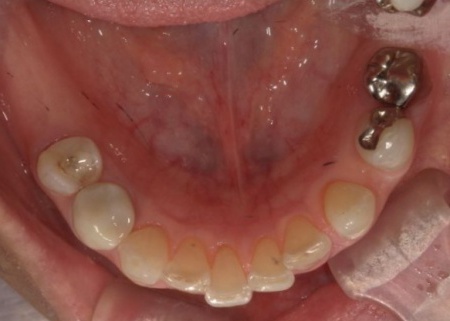

拝見したところ、左上奥歯2本(第1小臼歯、第2小臼歯)の被せ物が外れていたため、レントゲン撮影で詳しく検査をした結果、歯根が折れていることが確認できました。

まずは局所麻酔を行い、左上奥歯(第2小臼歯)を抜きます。

次に、抜歯した穴の状態を慎重に確認しながら、インプラント体を適切な深さと方向に埋入しました。今回は、抜歯と同時にインプラントを埋入する「抜歯即時埋入」を実施しています。

また、手前の歯にも新しい被せ物を装着しました。